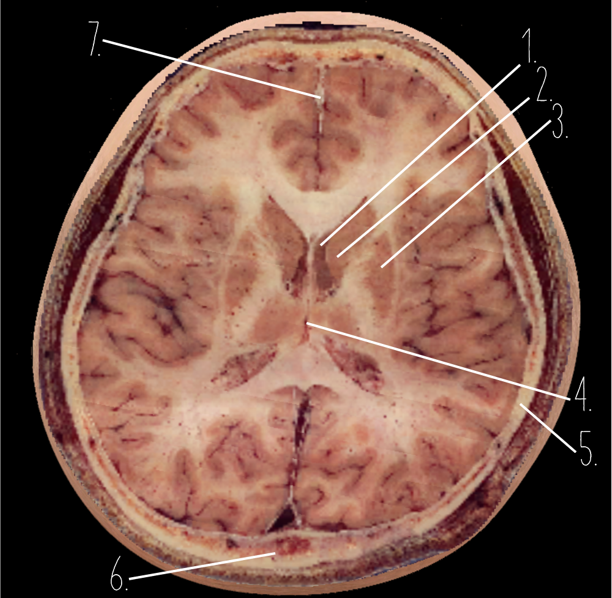

Brain Cross Sectional

1?

Parietal Lobe

2?

Cerebellum

3?

Occipital Bone

4?

Cerebellum

5?

Lateral Ventricle

6?

Frontal Bone

7?

Corpus Callosum

8?

Thalamus

9?

Hypothalamus

10?

Midbrain